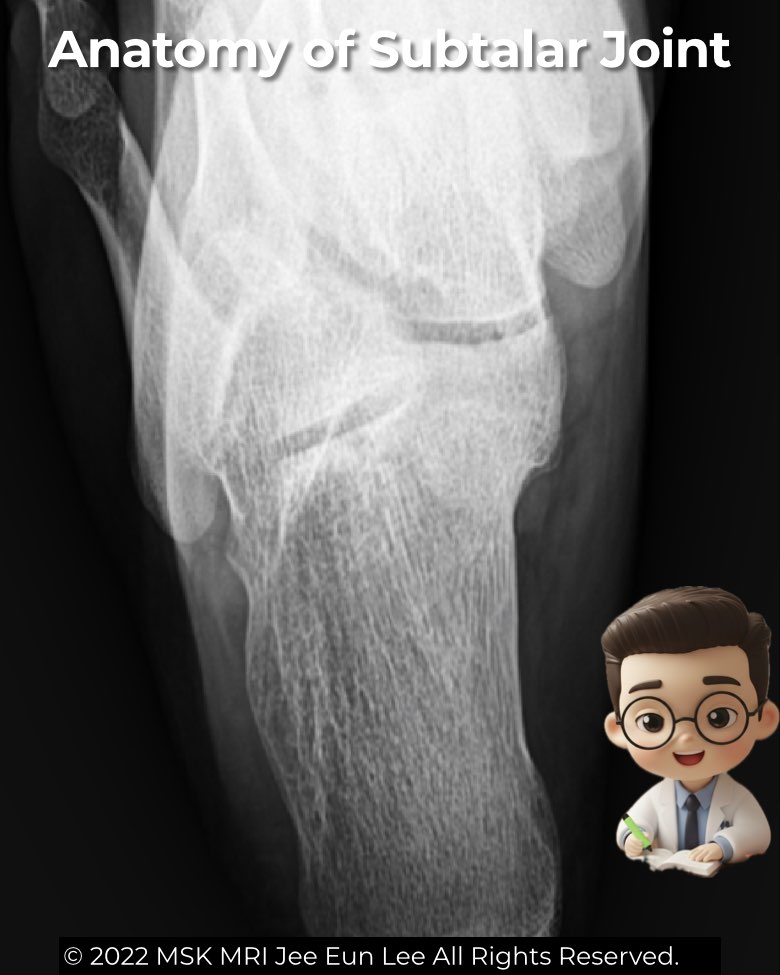

Harris Heel View: The Radiologist’s Shortcut to the Subtalar Joint

The Harris heel (axial) view is a specialized radiographic projection for the subtalar joint, especially the middle facet—key for detecting talocalcaneal coalition.

- Technique: patient standing with knee flexed or prone with dorsiflexed ankle; X-ray beam angled ~45° through the calcaneus.

- Normal: sustentaculum tali is clear, posterior and middle facets appear parallel, anterior facet is obscured.

- Coalition clues: loss of facet parallelism, joint space narrowing, irregularity, osseous bar, or fibrocartilaginous cleft with sclerosis or cysts.

Though CT and MRI are now preferred for detailed evaluation, the Harris heel view still offers valuable insight when coalition is suspected but subtle on routine views.